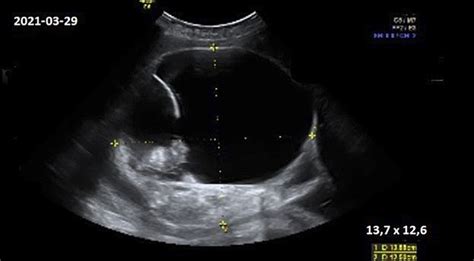

Diagnozė dažniausiai patvirtinama echoskopijos metu, kai:

- nėra vaisiaus širdies plakimo,

- embrionas mažesnis nei turėtų būti pagal nėštumo savaites,

- matomas tik tuščias gemalo maišelis.

Gydytojas gali sekti žmogaus chorioninio gonadotropino (hCG) hormono lygį kraujyje, kuris turėtų stabiliai didėti nėštumo metu. Tai yra pagrindinis diagnostikos metodas.